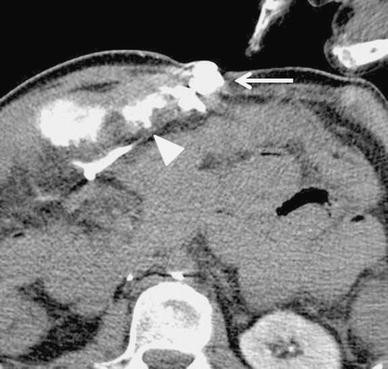

No active bleeding was identified by esophagogastroduodenoscopy and colonoscopy. Mesenteric variceal rupture into the small intestine was suspected because on contrast-enhanced CT scans, we observed mesenteric varices via small abdominal wall veins and thrombosis in the superior mesenteric vein (Fig. 1). On fusion images of SPECT using 99mTc-pyrophosphate (370 MBq) and nonenhanced helical CT images, a dense accumulation of mesenteric varices was seen. Conservative management with fasting did not improve his progressive anemia or melena. We obtained his prior written, informed consent for angiography and RTO using NBCA or 5 % ethanolamine oleate (EOI) and for inclusion in our study.

Contrast-enhanced CT scan reveals mesenteric varices (arrow) feeding the abdominal wall vein. All varices were directly connected. There is thrombosis in the mesenteric vein (arrowhead)